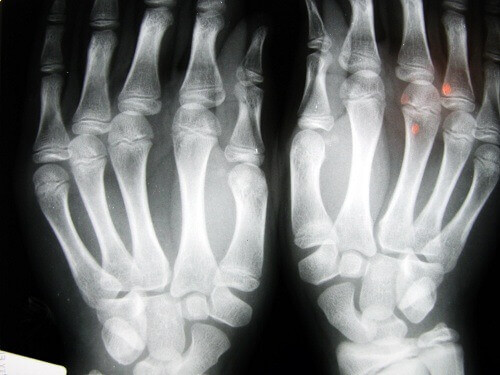

Робилися спроби оглянути різних людей, які часто хрустять суглобами, щоб з’ясувати, чи є пошкодження суглобів у вигляді артриту або остеоартриту.

У ході цього дослідження було виявлено, що пальці мають ознаки пошкодження, такі як травми м’яких тканин і зниження здатності хапати об’єкт. Здається, це пов’язано з швидким і повторюваним розтягуванням і стисканням зв’язок суглобів.

Чи виникне артрит, якщо хрустіти суглобами?

Багато людей запитують, чи може хрустіння кісточками пальців або розтягування суглобів призвести до появи артриту. Як вже згадувалося, якщо це звичайна, щоденна звичка, наявна протягом багатьох років, в теорії хрящі ушкоджуються.

У ході ще одного дослідження обстежили 30 літніх людей у будинку пристарілих в Лос-Анджелесі. Ті, хто хрустів кістками все своє життя, не мали остеоартриту. У третьому дослідженні, цього разу з дорослими 45 років в Детройті, було виявлено, що основна проблема полягає у втраті міцності в руках, і що понад 80% страждали від опухлих рук.